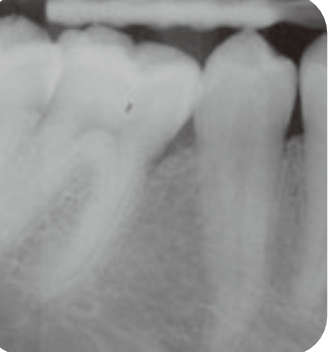

🦷 X-ray 비교

BEFORE

AFTERX-ray 상으로 명확하게 보이는 뼈 재생 효과

📈 Long-term Follow-up Cases

1Patient 1: 8년 장기 추적 케이스

치료 시작 전 상태

뼈 재생 진행 확인

재생된 뼈의 장기 유지 확인

✨ 핵심 포인트: Emdogain 치료 후 3년에 걸쳐 점진적으로 재생된 치조골이 8년이 지난 후에도 안정적으로 유지되고 있음을 확인할 수 있습니다. 이는 Emdogain의 장기적인 효과와 안정성을 보여주는 중요한 임상 증거입니다.